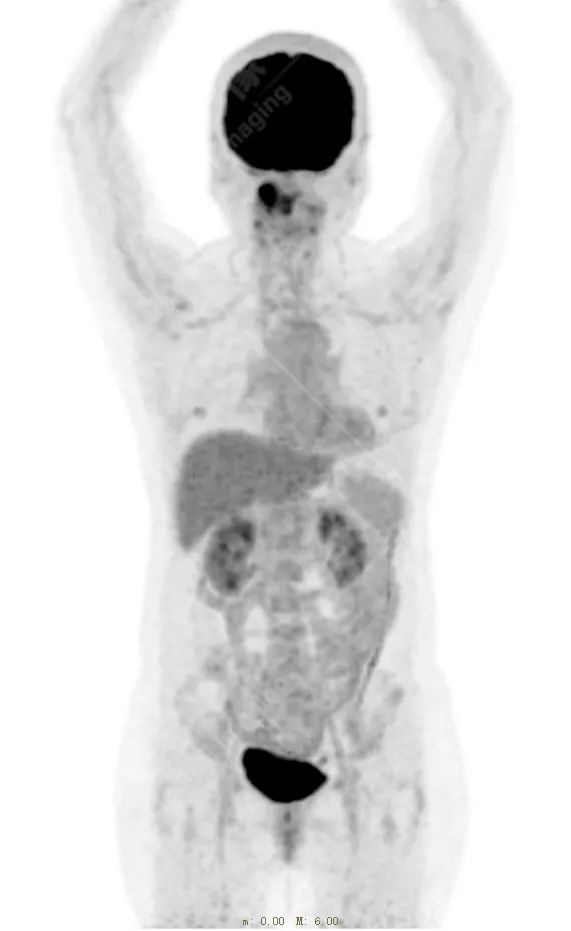

右侧上颌骨-上颌窦骨壁-骨性鼻中隔区域见片块状放射性摄取异常增高影,最大层面约 4.1 cm×3.8 cm×2.8 cm,SUV 最大值为 10.4,CT 示上述部位见成骨性改变,骨质不均匀弥漫性增厚、密度不均匀增高,并可见肿瘤骨影,边缘毛糙,周围伴软组织增厚。

根治性手术在放疗后骨肉瘤的治疗中是必须的,然而根治性手术仅仅适用于早期的病例,如本例病人,相对早期,周围组织结构无明显侵犯,PET 示肿瘤代谢也局限于肿瘤本体。